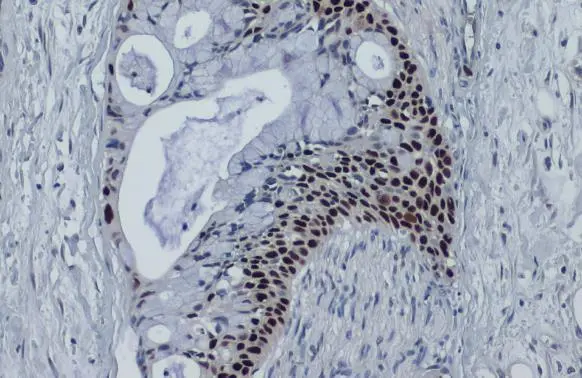

Anti-p53 antibody [DO1] used in IHC (Paraffin sections) (IHC-P). GTX70214

GTX70214 IHC-P Image

p53 antibody [DO1] detects p53 protein at nucleus by immunohistochemical analysis.

Sample: Paraffin-embedded human oral carcinoma.

p53 stained by p53 antibody [DO1] (GTX70214) diluted at 1:100.

Antigen Retrieval: Citrate buffer, pH 6.0, 15 min

4 / 14